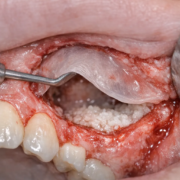

Traitement de la péri-implantite (atteinte osseuse)

La prise en charge est individualisée (selon profondeur des poches, perte osseuse, type de prothèse, facteurs de risque). Les recommandations incluent généralement :

• instructions d’hygiène + contrôle des facteurs de risque

• nettoyage professionnel supra- et sous-gingival, gestion des zones qui retiennent la plaque

• traitement parodontal associé si nécessaire

• selon les cas : stratégies complémentaires et parfois chirurgie (objectif : contrôler l’infection et stabiliser l’os)

Dans tous les cas, plus la prise en charge est précoce, meilleures sont les chances de stabiliser la situation.